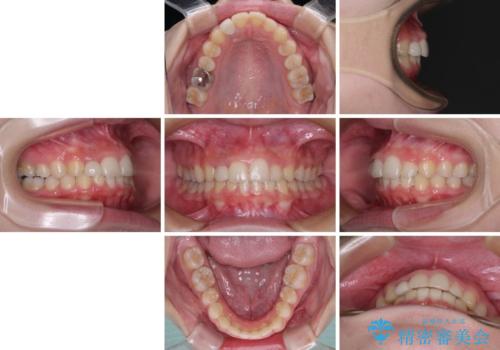

- 前歯の歯並びと不自然な色をした前歯のクラウンを気にして来院された患者様です。

上下前歯の歯列不正はインビザラインにより歯列を整え、その後に、前歯をオーダーメイドタイプのオールセラミッククラウンにて補綴治療することとしました。

前歯のデコボコを一番気にしていらっしゃいましたが、矯正治療により下顎前歯が隠れるほどのディープバイトも一緒に改善され、奥歯に負担のかかりにくい咬み合わせとなりました。